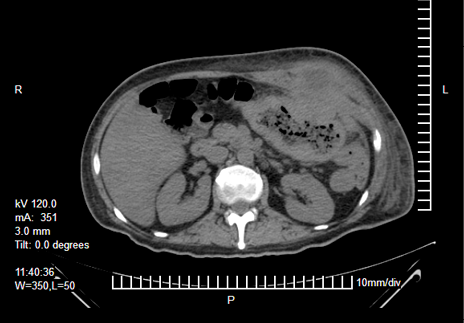

Laboratorios a su ingreso: hemoglobina 9,3 g/dL, hematocrito 29,6 %, plaquetas 574 x 109/L y albumina 1,6 g/dL, resto dentro de parámetros normales. Se realizó una tomografía abdominal que reportó un tumor dependiente del colon transverso con invasión a pared abdominal y formación de absceso (Figura 1, 2 y 3). Con el paciente en estado séptico, se decide el drenaje y la exploración quirúrgica previa estabilización.

Figura 2. Engrosamiento de la pared del colon transverso, con pérdida de la interfase hacia la pared abdominal y colección líquida a nivel de la unión del recto anterior del abdomen y los músculos oblicuos. Fuente: archivo electrónico del HGZ No. 35 (IMSS).

Figura 3. Corte sagital donde se observa la tumoración del colon transverso y su invasión a la pared abdominal. Fuente: archivo electrónico del HGZ No. 35 (IMSS).